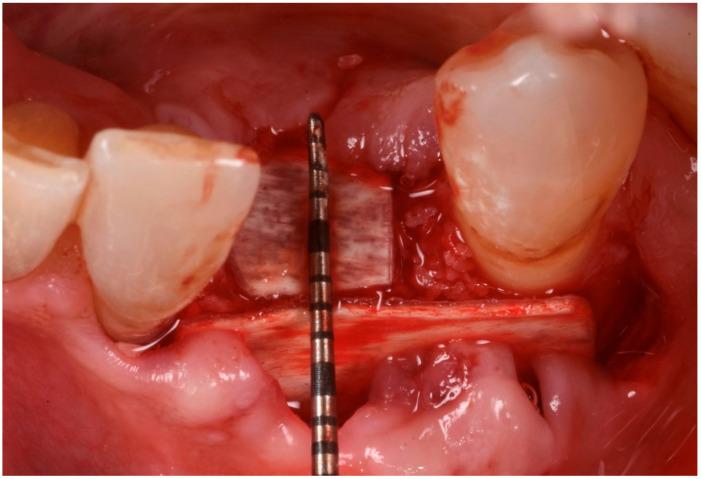

Guided bone regeneration (GBR) has represented a challenge for clinicians in the past 30 years, and the literature has well described many different surgical options such as d-PTFE membranes, titanium grids, or autogenous bone harvested from the posterior mandible. All of the previously mentioned techniques have shown a high rate of complications but, in the last decade, a new membrane made of xenogenic bone was introduced. Most of the publications regarding its application report very few and mild complications. In this article we will suggest a new application using segmented xenogenic bone sheets instead of autogenous bone to correct severe ridge deformity. : Xenogenic bone sheets have been studied extensively over the past decade and have proven effective, with a very low rate of complications when used to reconstruct bone atrophies. The technique presented in this paper aims to reduce morbidity, avoid the need for intra-oral graft harvesting, and minimize both surgical time and post-operative discomfort. : Xenogenic bone sheets of equine origin were used to reconstruct severe 3D bone defects in five patients requiring dental implants. The segmentation of the sheet allowed the operator to rebuild the missing bone walls and achieve optimal anatomy without compromise. Furthermore, using different sizes and thicknesses of the bone sheets allowed safe procedures preventing early exposure of the membranes. CBCT of the defects before and after 8 months of healing were measured with Exocad software to assess the volumetric gain. Histological analysis performed on one site showed integration of the bone lamina and live bone underneath. : In all five cases evaluated the ridge deformities were successfully corrected and all patients' implants have functioned for more than two years to date. The average horizontal bone gain in these five cases was 6.18 mm (±1.19 mm) while the vertical gain was 9.70 mm (±2.39 mm). : This new application of flex cortical sheets simplifies the surgical procedure for both operator and patient, reduces morbidity and post-operative complications, and shows promising signs for resolving complex 3D bone reconstructions.

在过去30年里,引导骨再生(GBR)一直是临床医生面临的一项挑战,文献中已经详细描述了许多不同的手术选择,如双层聚四氟乙烯(d-PTFE)膜、钛网或从下颌后部获取的自体骨。上述所有技术都显示出较高的并发症发生率,但在过去十年中,一种由异种骨制成的新型膜被引入。关于其应用的大多数出版物报告的并发症很少且很轻微。在本文中,我们将提出一种使用分段异种骨片代替自体骨来矫正严重牙槽嵴畸形的新应用。:在过去十年中,异种骨片已被广泛研究,并已被证明是有效的,用于重建骨萎缩时并发症发生率非常低。本文介绍的技术旨在降低发病率,避免口内取骨的需要,并将手术时间和术后不适降至最低。:使用马源异种骨片为五名需要种植牙的患者重建严重的三维骨缺损。骨片的分段使手术者能够重建缺失的骨壁并实现最佳解剖结构而不受影响。此外,使用不同尺寸和厚度的骨片可进行安全操作,防止膜过早暴露。使用Exocad软件测量愈合8个月前后缺损的锥形束计算机断层扫描(CBCT),以评估体积增加情况。对一个部位进行的组织学分析显示骨板与下方活骨的整合。:在评估的所有五例病例中,牙槽嵴畸形均得到成功矫正,所有患者的种植体至今已正常使用两年多。这五例病例的平均水平骨增量为6.18毫米(±1.19毫米),而垂直增量为9.70毫米(±2.39毫米)。:这种柔性皮质骨片的新应用简化了手术者和患者的手术过程,降低了发病率和术后并发症,并显示出解决复杂三维骨重建问题的良好前景。